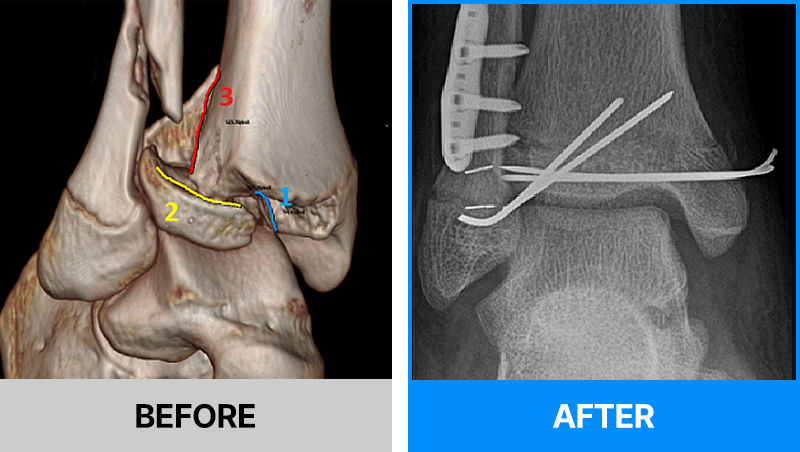

왜 당일 입퇴원 수술일까요?

오래 입원할 필요가 없기 때문입니다.

서울거탑정형외과에서는 전신마취, 척추마취가 아닌

국소부분마취(신경차단) 및 수면 마취를 통해 수술을 시행합니다.

수술 가능 여부 확인은 대표원장과의 진료가 필요합니다.